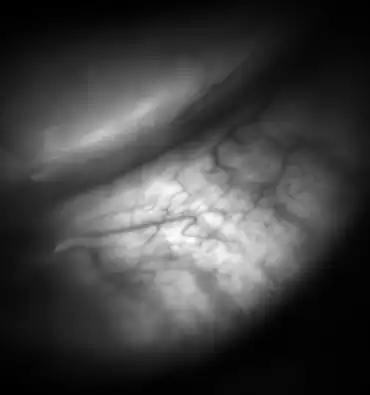

![Meibomian glands in the lower eyelid imaged under amber light to show vasculature support and the gland structure [epiCam].](./_assets_/0c70a452f799bfe840676ee341124611/Meibomian-glands.png)

Dysfunctional meibomian glands often cause dry eyes, one of the more common eye conditions. They may also contribute to blepharitis. Inflammation of the meibomian glands (also known as meibomitis, meibomian gland dysfunction, or posterior blepharitis) causes the glands to be obstructed by thick, cloudy-to-yellow, more opaque and viscous-like, oily and waxy secretions, a change from the glands' normal clear secretions.[12][13] Besides leading to dry eyes, the obstructions can be degraded by bacterial lipases, resulting in the formation of free fatty acids, which irritate the eyes and sometimes cause punctate keratopathy.